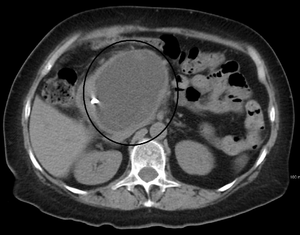

| A pancreatic pseudocyst as seen on CT | |

A pancreatic pseudocyst is a circumscribed collection of fluid rich in pancreatic enzymes, blood, and necrotic tissue, typically located in the lesser sac of the abdomen. Pancreatic pseudocysts are usually complications of pancreatitis,[1] although in children they frequently occur following abdominal trauma. Pancreatic pseudocysts account for approximately 75% of all pancreatic masses.[2]

- Computerized tomography[9] – This is the gold standard for initial assessment and follow-up.